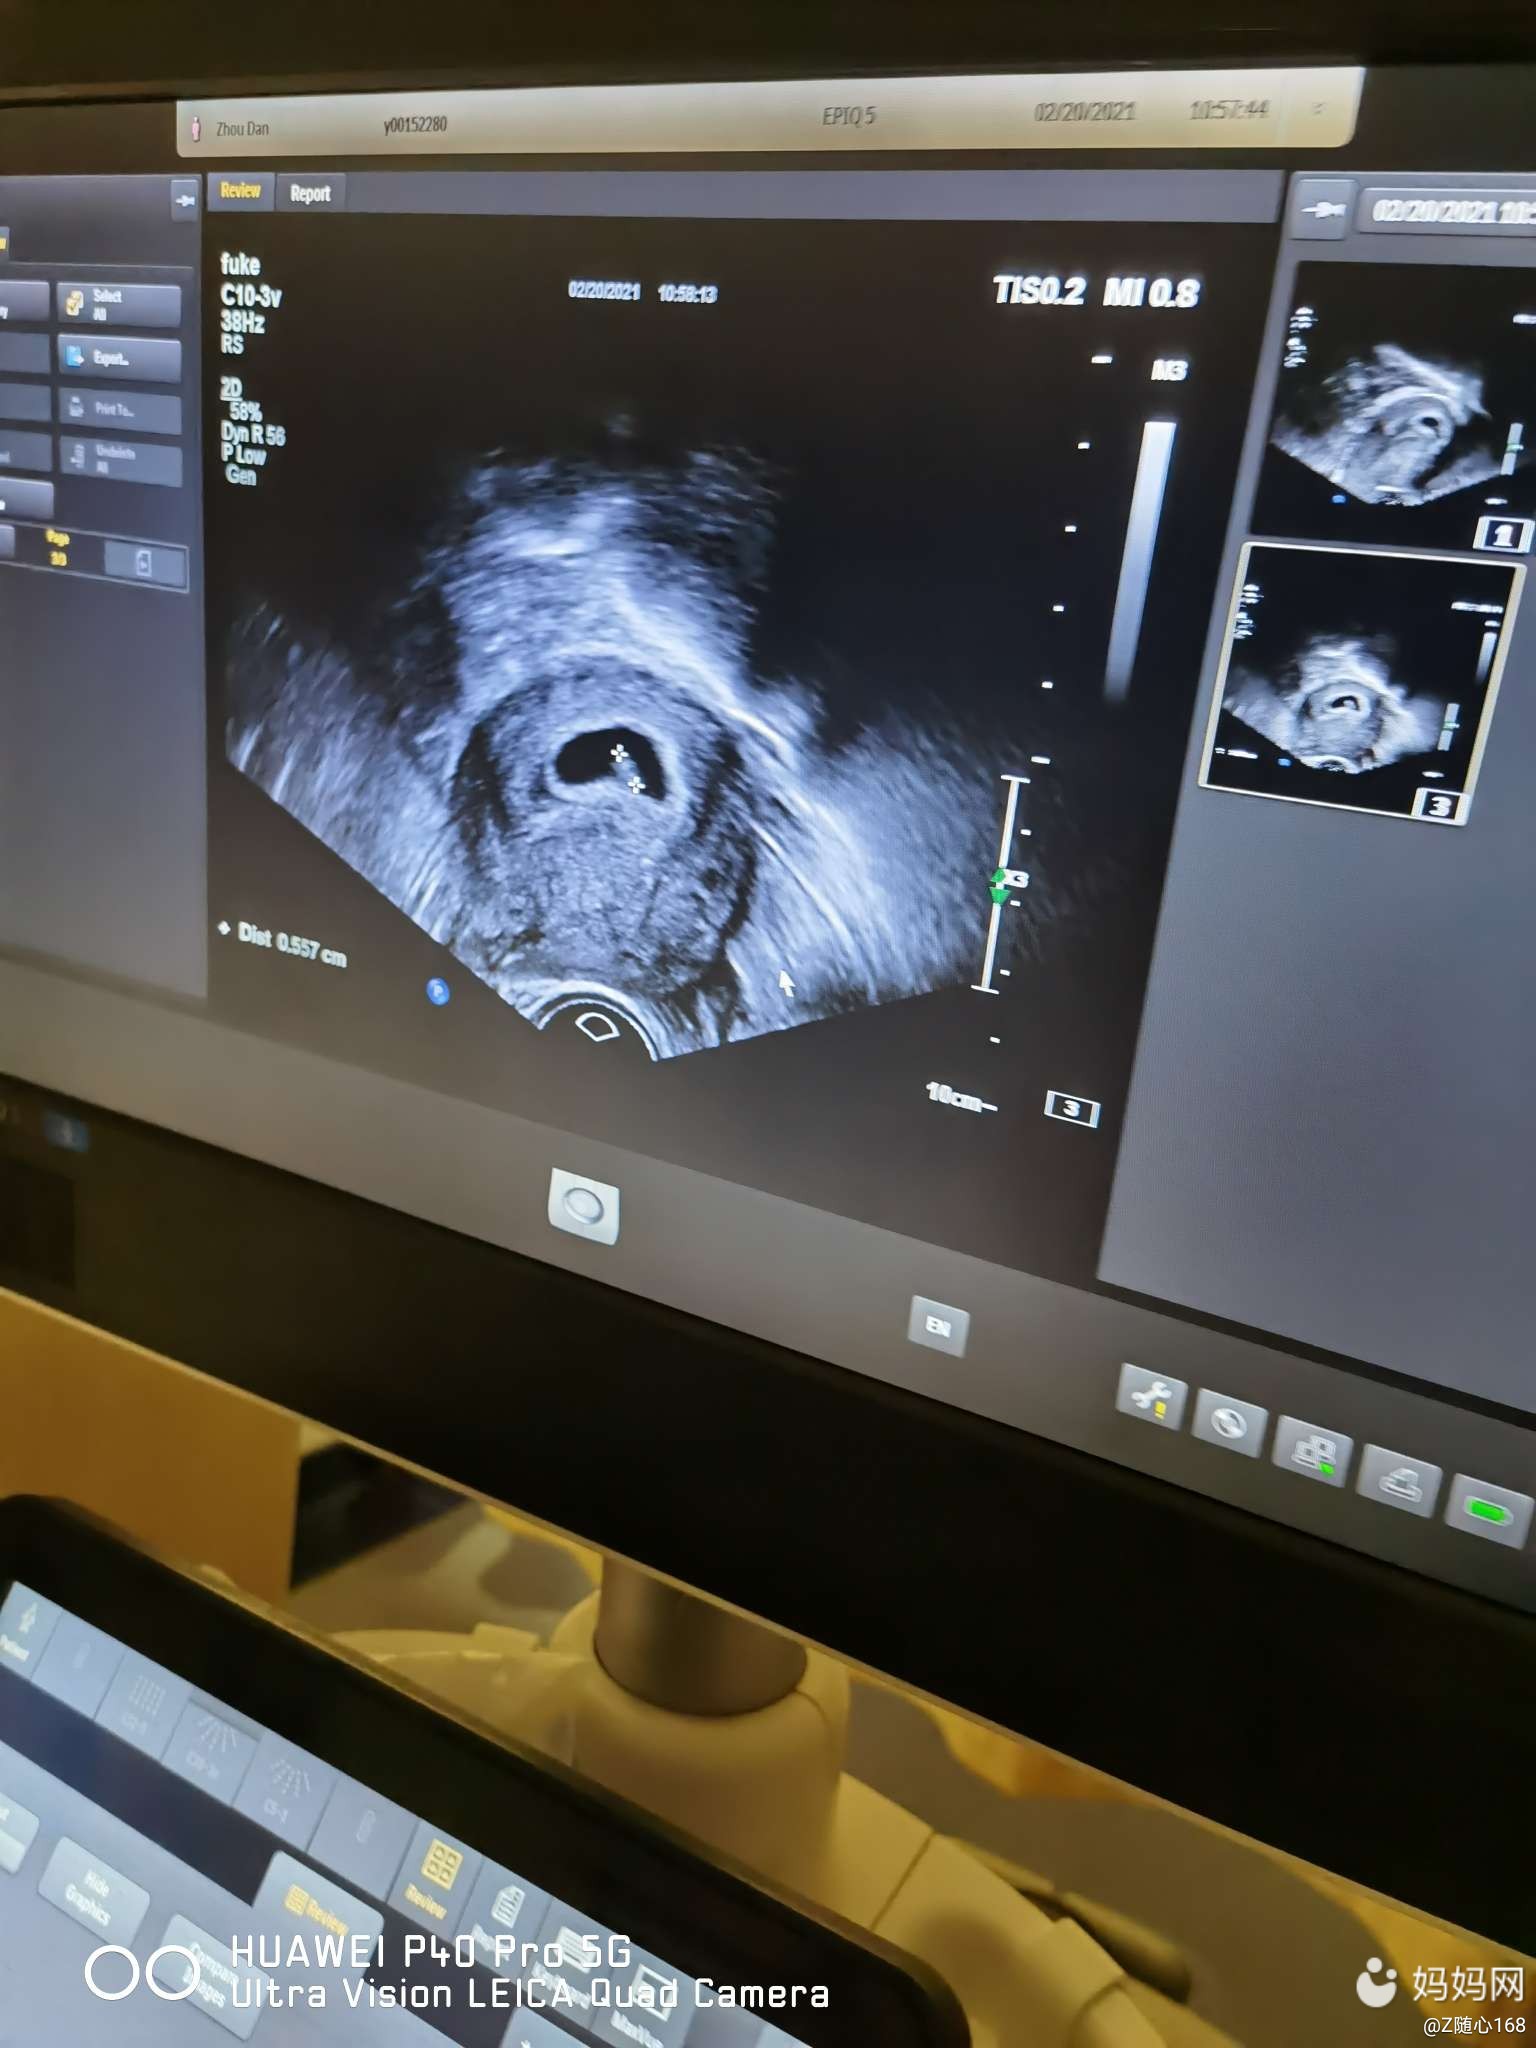

孕囊是茄子形状的让保胎看效果09

孕8周的孕囊,这是什么形状啊,都说茄子和长条大多是_妈妈网孕育社区

二胎记录 1,7周检查孕囊长条茄子形状,大宝女娃是圆形.